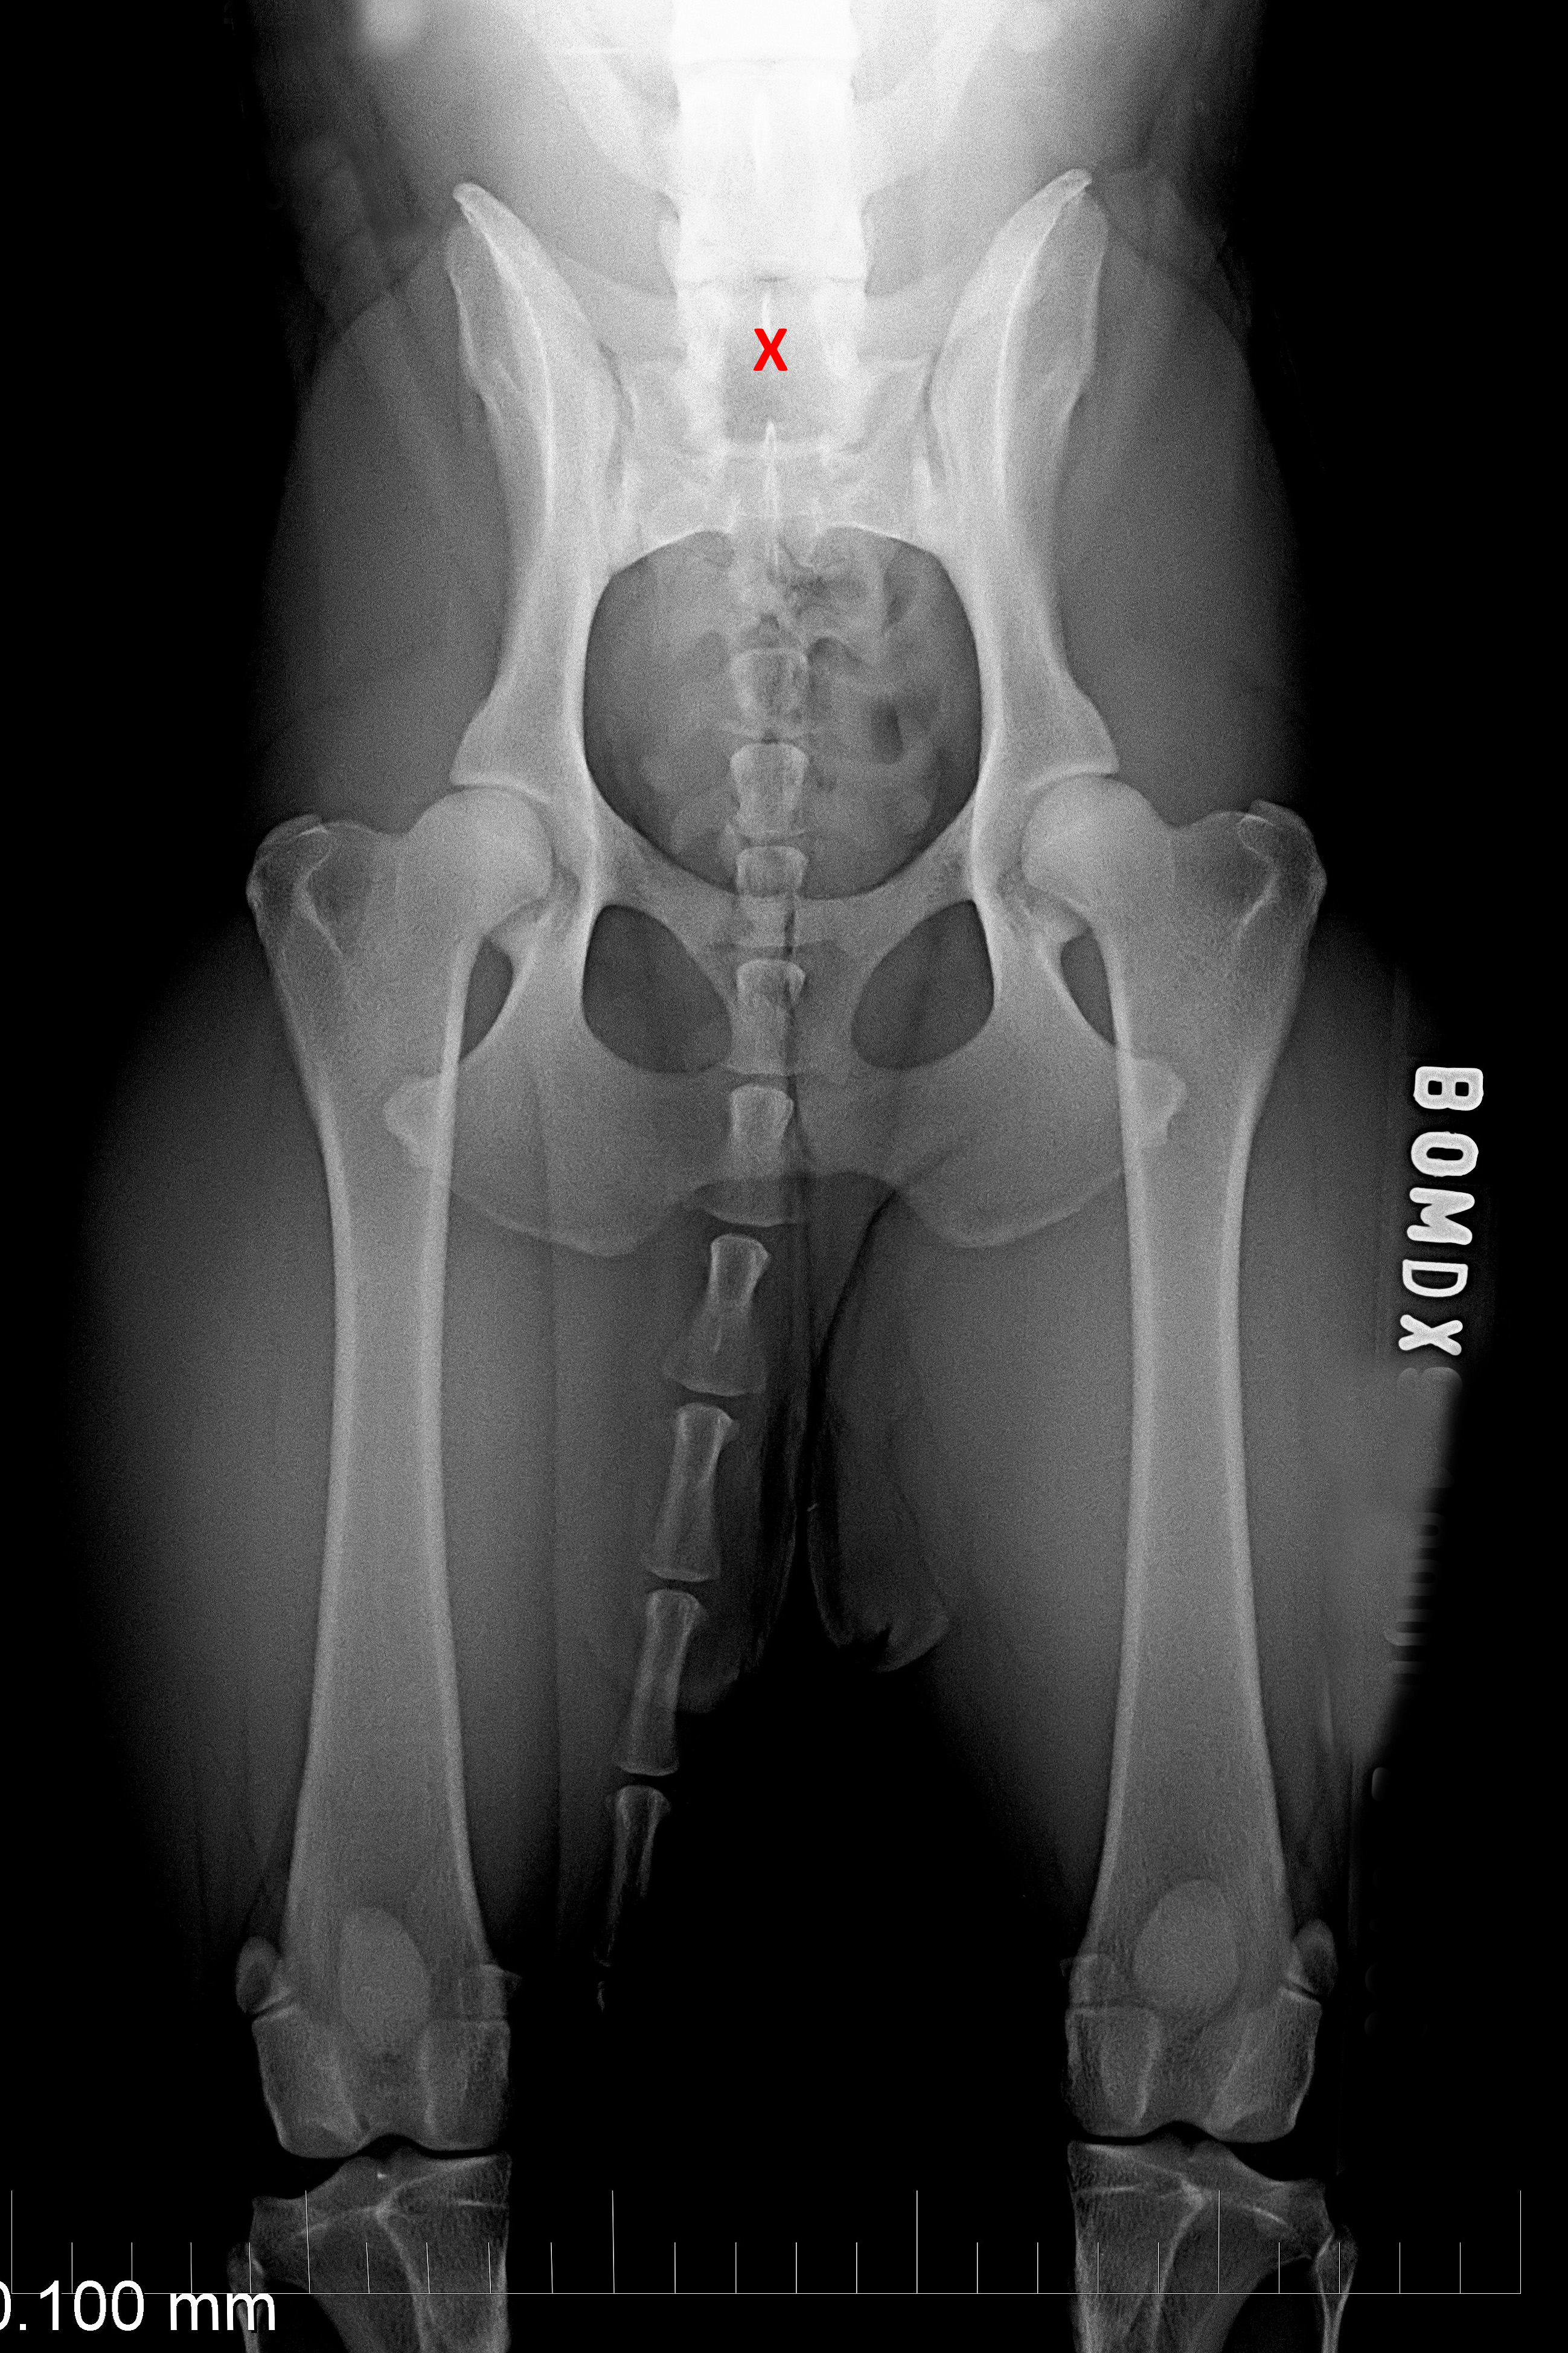

(1) 7 týdnů VD

(1) typ 3

(3) 7 měsíců VD 1

(3) typ 3 po korekci polohy pánve

(4) 7 měsíců VD 2

(4) typ 3 po korekci polohy pánve 2